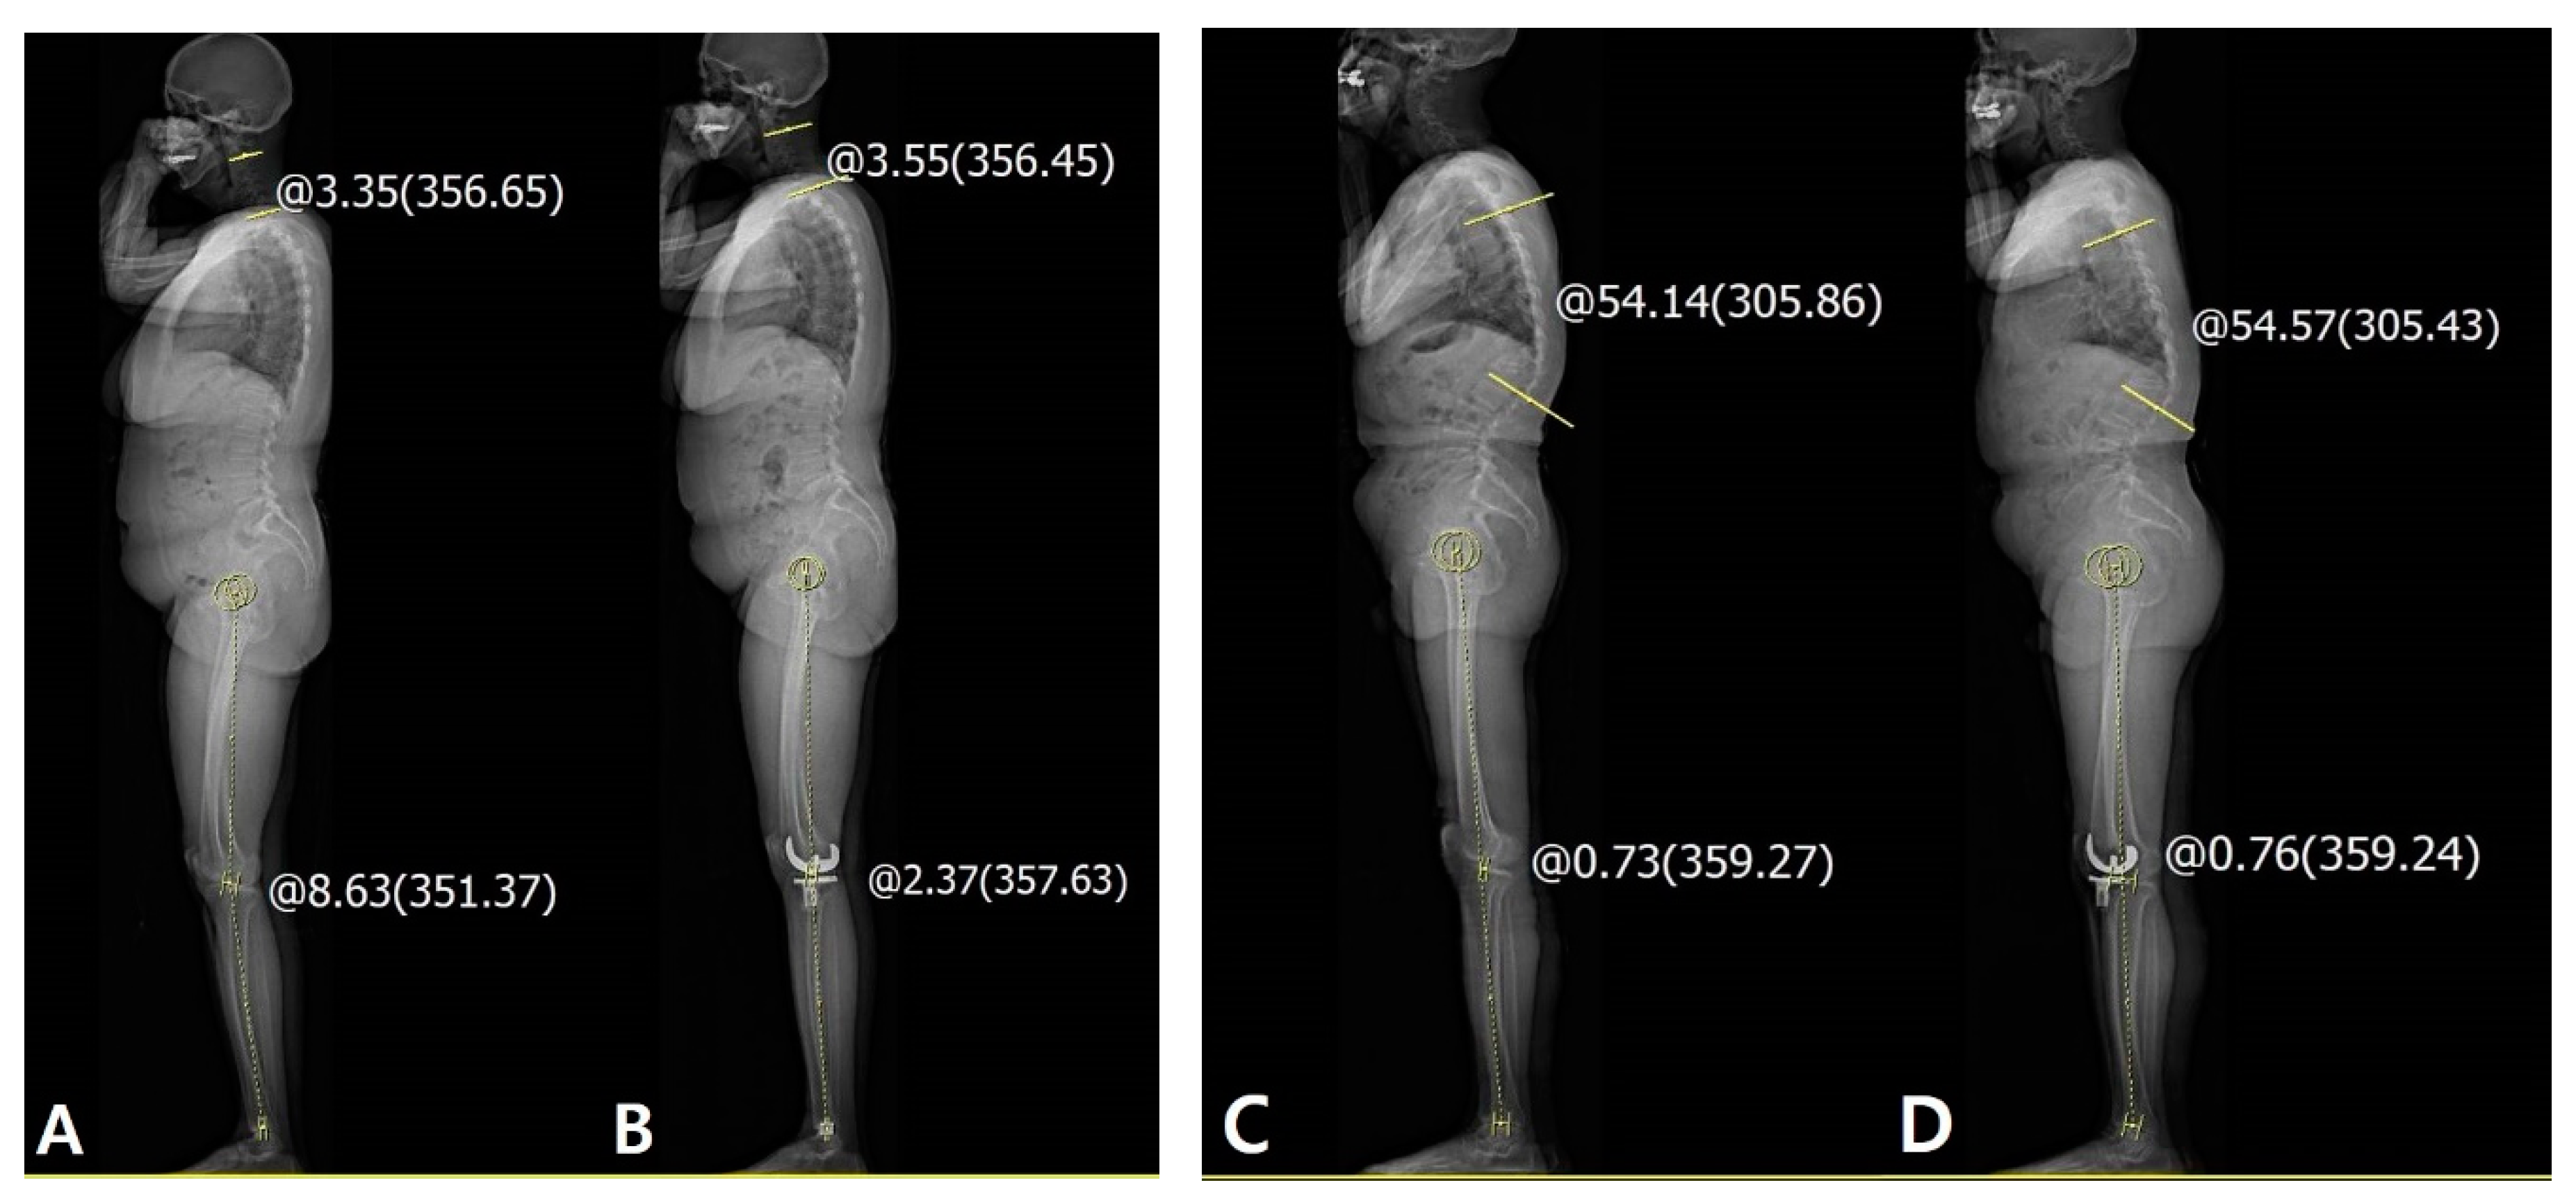

Figure 6. Cervical deformity showed little effect on the lower limb and spinal alignment itself. (A) Preoperative cervical lordosis: 3.35° and HKA angle: 8.63°. (B) Postoperative cervical lordosis: 3.55° and HKA angle: 2.37°. Thoracic deformity showed little effect on the lower limb and spinal alignment itself. (C) Preoperative thoracic kyphosis: 54.14° and HKA angle: 0.73°. (D) Postoperative thoracic kyphosis: 54.57° and HKA angle: 0.76°. The yellow line and circle are the measurement about sagittal HKA and cervical lordosis and thoracic kyphosis.

Interestingly, some patients demonstrated a tendency to stand with knee flexion even if the fixed knee flexion contracture was corrected and there was no flexion contracture in the clinical measurement. From our study, we believe that this disparity was mostly related to the reduced LF. Cervical or thoracic deformity showed limited effect on the lower limb or spinal alignment itself (Figure 6). Therefore, preoperative evaluation of the LF would be important for successful TKA. Since this disparity is associated with lumbar flat back or stooping during standing as a compensation mechanism, [14,15,16] it can be problematic in that the flexible knee extension status can become a fixed flexion contracture with time.